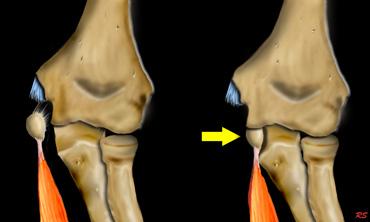

Extreme valgus

Cơ chế gãy xương quan trọng khác là tình trạng valgus cùi chỏ quá mức.

Khuỷu tay bình thường đã có tư thế valgus sẵn.

Khi trẻ ngã chống tay với cánh tay duỗi thẳng, điều này có thể dẫn đến valgus quá mức.

Ở phía ngoài, điều này có thể dẫn đến trật khớp hoặc gãy xương quay có hoặc không kèm theo tổn thương mỏm khuỷu.

Khi lực tác động nhiều hơn lên xương cánh tay, tình trạng valgus quá mức sẽ dẫn đến gãy lồi cầu ngoài.

Ở phía trong, lực valgus có thể dẫn đến bong lồi cầu trong.

Đôi khi lồi cầu trong bị kẹt trong khớp.

Do tư thế valgus của khuỷu tay bình thường, bong lồi cầu ngoài sẽ ít gặp hơn.